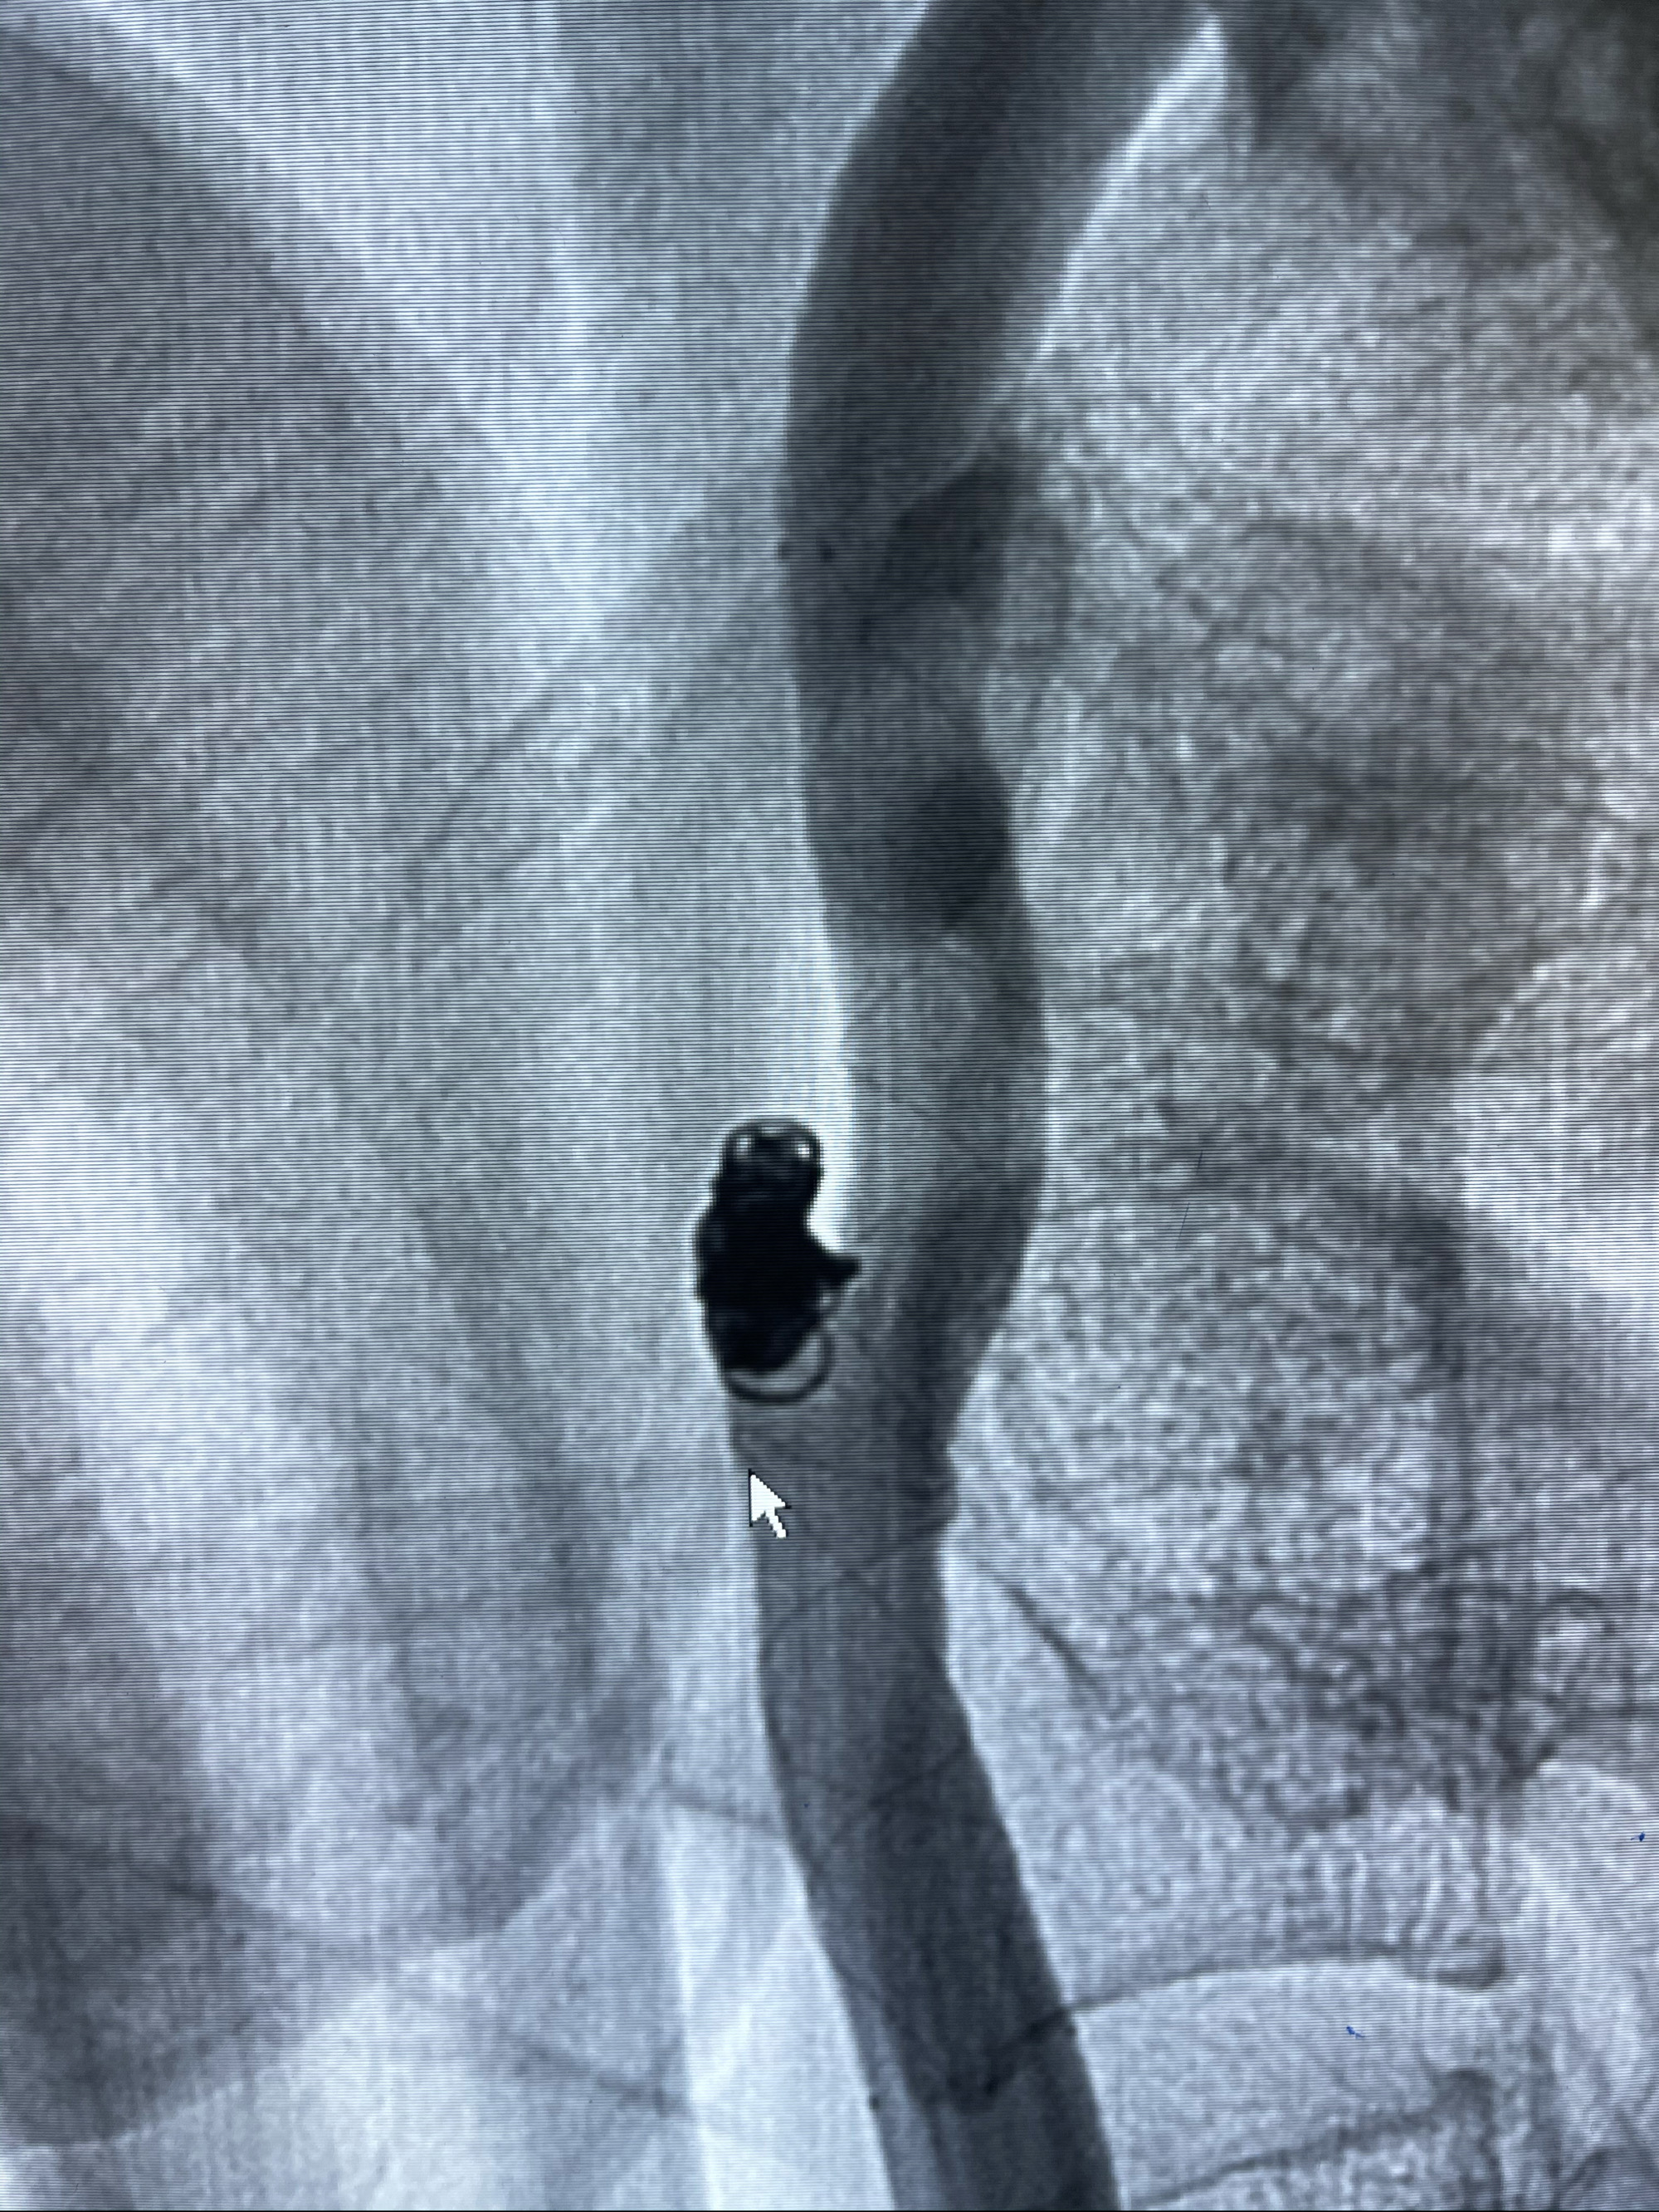

Eterprise4.0-23mm支架导管到位

Echelon10 45°角微导管塑形后到位

8mm-40cm微弹簧圈成篮

支架到位